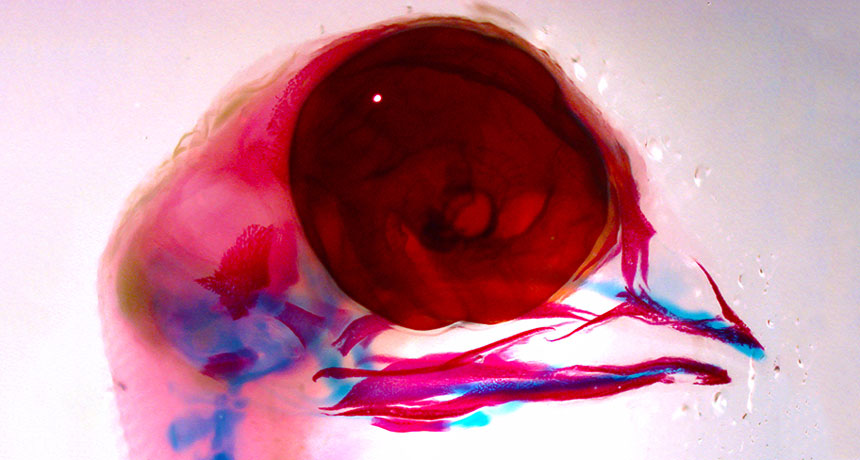

BASIC BEAK The red- and blue-stained facial features of this chick, which was incubated under standard laboratory temperatures, reveal an upper beak that is developing properly.

M. Hutson et al/Science Signaling 2017